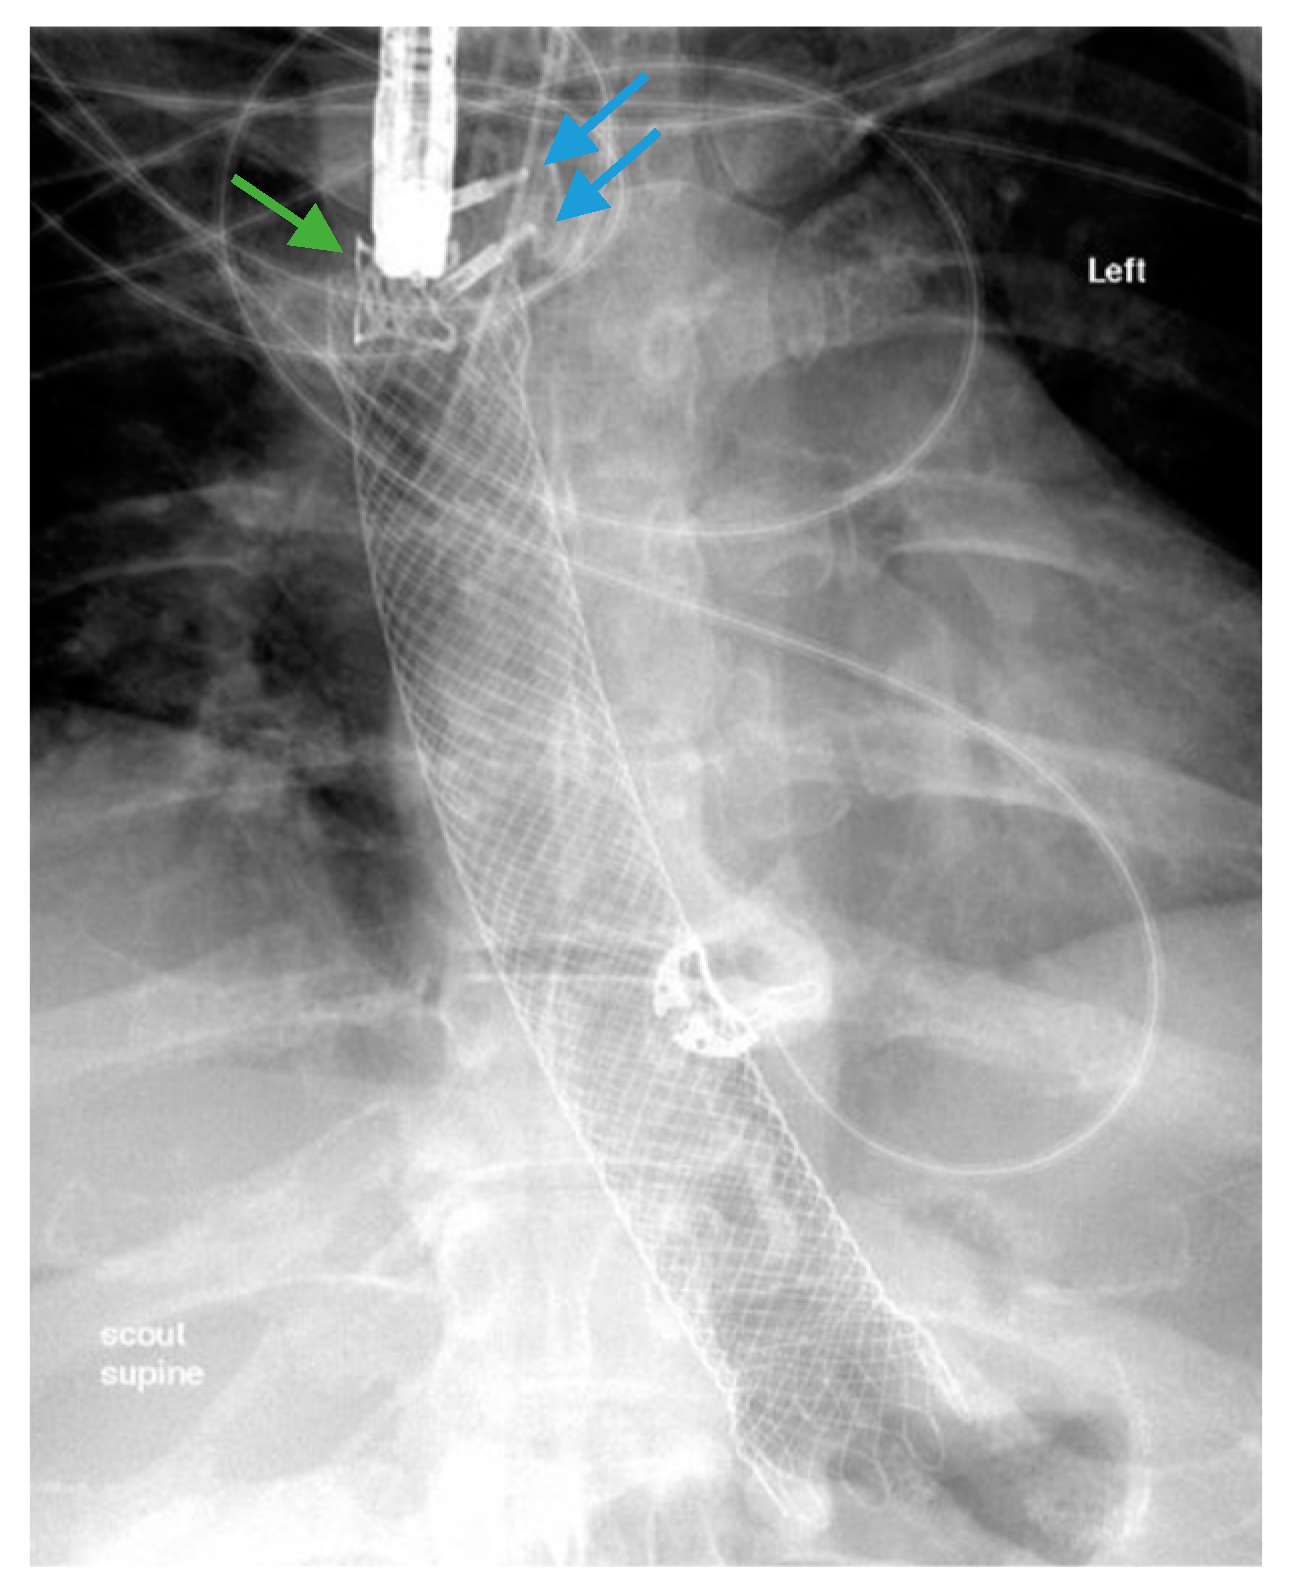

3.2. Endoscopic Stenting

3.3. Endoscopic Internal Drainage with Transgastric Double-Pigtail Stents